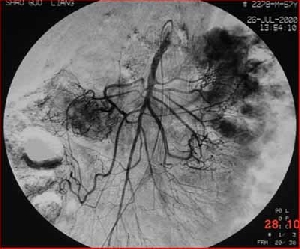

腸癌治療新選擇——介入+手術(shù)

有這么一種對(duì)付腫瘤的辦法:一方面將高濃度的藥物直接作用于局部,發(fā)揮最大的抗腫瘤作用,對(duì)全身毒副作用小,絕大部分患者能接受治療;另一方面,可將腫瘤的供血血管阻塞,